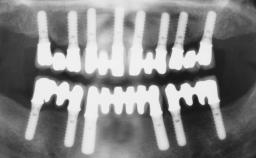

ITI Curriculum FL: Patient Assessment Case 10

Example intended for case-based discussion regarding patient assessment, diagnosis and determination of risk and complexity.

| Jaw | Maxilla and Mandible |

| Area | Posterior |